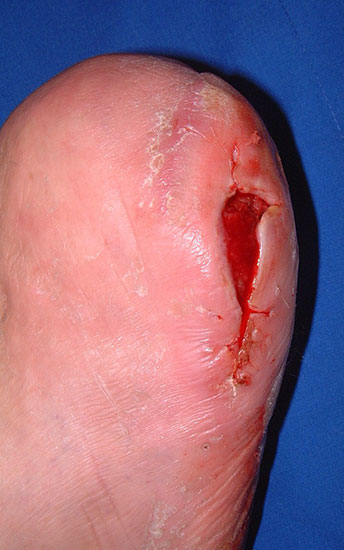

Seltene Indikationen:

• der nachvollziehbare Wunsch von multimorbiden Patienten nach einer kurzen Heilungszeit bzw. nach einer baldigen Belastbarkeit,

• wenn bei schweren Begleiterkrankungen v.a. bei höher gradiger Herz- oder Niereninsuffizienz rekonstruktive Behandlungen zu riskant oder nicht möglich sind;

• ungünstige Amputationssituationen, die keine angemessene schuh- oder orthopädietechnische Versorgung erlauben (Abb. 3).